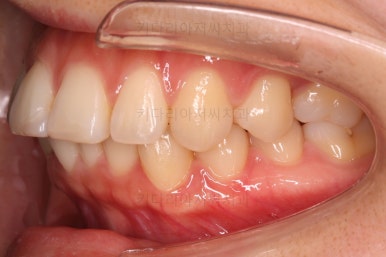

마찬가지로 부산연산동교정치과 초진 시 입안의 모습입니다.

아래 앞니도 삐뚤한 편이었고 아래 앞니가 불쑥 위로 올라와 있어서 이를 악 다물면 위아래 앞니가 많이 겹치는 "과개교합" 패턴이 나타나요.

윗니가 전반적으로 아랫니보다 앞에 나와 있어서 2급 부정교합에 윗니만 튀어나온 양상이고 이 때문에 윗니 앞니가 다치고 부러졌따가 떼운 흔적이 보이네요.